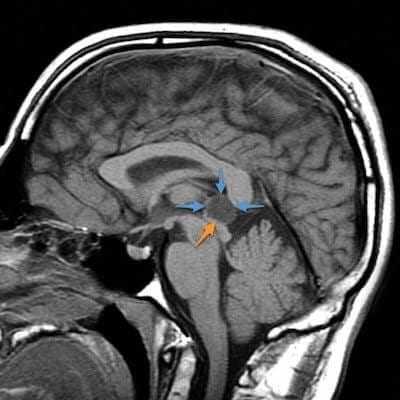

Пиллоидная астроцитома задних отделов III желудочка. Определяется небольших размеров образование с развитием окклюзионной гидроцефалии. Опухоль практически не отличается по сигналам от вещества головного мозга. После в/в контрастирование отмечается усиление МР-сигнала от образование, что позволяет уточнить расположение опухоли, степень компрессии четверохолмной пластинки и водопровода мозга.

Киста эпифиза. Компрессия четверохолмной пластинки и частичное сдавление водопровода мозга.